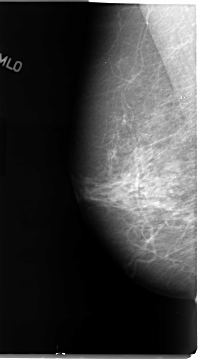

B_3094_1.LEFT_CC

LEFT_CC LINES 4664 PIXELS_PER_LINE 2584 BITS_PER_PIXEL 12 RESOLUTION 50 OVERLAY

FILE: B_3094_1.LEFT_CC.OVERLAY

TOTAL_ABNORMALITIES 1

ABNORMALITY 1

LESION_TYPE CALCIFICATION TYPE AMORPHOUS DISTRIBUTION CLUSTERED

ASSESSMENT 3

SUBTLETY 2

PATHOLOGY BENIGN

TOTAL_OUTLINES 1

BOUNDARY